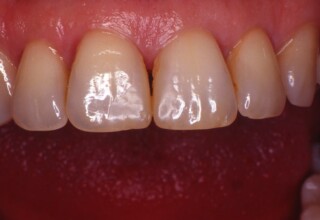

Whitening of non-vital teeth

Teeth with a root canal often lose their brightness and darken to an unesthetic level. Their bleaching requires an excellent root canal and patience. An adhesive filling is placed inside the root to confine the bleaching effect to the tooth part which is visible in the oral cavity. The actual bleaching may require 1-5 short sessions for the placement and renewal of the bleaching material. After the bleaching a high quality adhesive filling is mandatory.